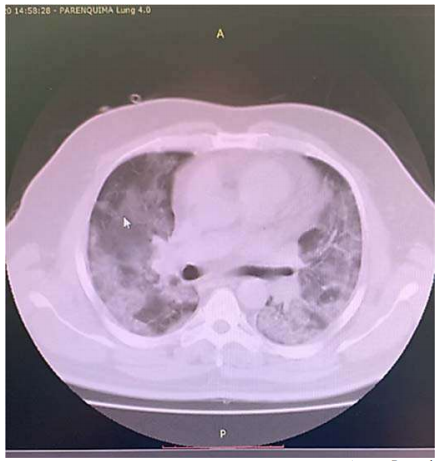

Um paciente de 68 anos de idade, com RT PCR para Sars-CoV-2 reagente (VR = não reagente), evolui com astenia, inapetência, tosse seca e coriza nasal. Realiza exames de imagem, no quinto dia de doença, em tomógrafo de alta definição, em que foram descritas lesões em vidro fosco bilaterais, correspondendo a 25% dos pulmões, podendo estarem associadas a processo inflamatório/infeccioso viral. Segue em acompanhamento domiciliar da doença. No 12º dia de doença, o paciente retorna com rouquidão, cianose de extremidades, apresentando febre de 38 o C e desconforto respiratório com uso de musculatura acessória. Verificam-se ausculta pulmonar com tórax silente, SatO2 = 78% com 15 litros / minuto de oxigênio em máscara facial com reservatório, PA = 87 mmHg x 43 mmHg, FC = 123 bpm e FR = 52 irpm. Os exames indicaram os seguintes resultados: leucograma = 5.400, sem desvios; PCR (proteína C reativa) = 356 (VR = abaixo de 6); ferritina = 11.458 ng/mL (VR = 20 ng/mL a 330 ng/mL); dímero -D = 26 mcg/mL (VR = 0,5 mcg/mL); gasometria pH = 7,109 (VR = 7,35 a 7,45); PaO2 = 53,8 mmHg (VR = 80 mmHg a 100 mmHg); PaCO2 = 104,6 mmHg (VR = 35 mmHg – 45 mmHg); HCO3 = 21 mmol/L (VR = 21 mmol/L a 28 mmol/L); SaO2 = 76,7 % (VR = 95% a 99%). Foi realizada nova tomografia do paciente, cuja imagem parcial pode ser observada a seguir.

Acervo Pessoal

Com base nesse caso clínico, na imagem da tomografia apresentada e nos conhecimentos médicos correlatos, julgue os itens a seguir.

Um paciente de 68 anos de idade, com RT PCR para Sars-CoV-2 reagente (VR = não reagente), evolui com astenia, inapetência, tosse seca e coriza nasal. Realiza exames de imagem, no quinto dia de doença, em tomógrafo de alta definição, em que foram descritas lesões em vidro fosco bilaterais, correspondendo a 25% dos pulmões, podendo estarem associadas a processo inflamatório/infeccioso viral. Segue em acompanhamento domiciliar da doença. No 12º dia de doença, o paciente retorna com rouquidão, cianose de extremidades, apresentando febre de 38 o C e desconforto respiratório com uso de musculatura acessória. Verificam-se ausculta pulmonar com tórax silente, SatO2 = 78% com 15 litros / minuto de oxigênio em máscara facial com reservatório, PA = 87 mmHg x 43 mmHg, FC = 123 bpm e FR = 52 irpm. Os exames indicaram os seguintes resultados: leucograma = 5.400, sem desvios; PCR (proteína C reativa) = 356 (VR = abaixo de 6); ferritina = 11.458 ng/mL (VR = 20 ng/mL a 330 ng/mL); dímero -D = 26 mcg/mL (VR = 0,5 mcg/mL); gasometria pH = 7,109 (VR = 7,35 a 7,45); PaO2 = 53,8 mmHg (VR = 80 mmHg a 100 mmHg); PaCO2 = 104,6 mmHg (VR = 35 mmHg – 45 mmHg); HCO3 = 21 mmol/L (VR = 21 mmol/L a 28 mmol/L); SaO2 = 76,7 % (VR = 95% a 99%). Foi realizada nova tomografia do paciente, cuja imagem parcial pode ser observada a seguir.

Acervo Pessoal

Com base nesse caso clínico, na imagem da tomografia apresentada e nos conhecimentos médicos correlatos, julgue os itens a seguir.

Um paciente de 68 anos de idade, com RT PCR para Sars-CoV-2 reagente (VR = não reagente), evolui com astenia, inapetência, tosse seca e coriza nasal. Realiza exames de imagem, no quinto dia de doença, em tomógrafo de alta definição, em que foram descritas lesões em vidro fosco bilaterais, correspondendo a 25% dos pulmões, podendo estarem associadas a processo inflamatório/infeccioso viral. Segue em acompanhamento domiciliar da doença. No 12º dia de doença, o paciente retorna com rouquidão, cianose de extremidades, apresentando febre de 38 o C e desconforto respiratório com uso de musculatura acessória. Verificam-se ausculta pulmonar com tórax silente, SatO2 = 78% com 15 litros / minuto de oxigênio em máscara facial com reservatório, PA = 87 mmHg x 43 mmHg, FC = 123 bpm e FR = 52 irpm. Os exames indicaram os seguintes resultados: leucograma = 5.400, sem desvios; PCR (proteína C reativa) = 356 (VR = abaixo de 6); ferritina = 11.458 ng/mL (VR = 20 ng/mL a 330 ng/mL); dímero -D = 26 mcg/mL (VR = 0,5 mcg/mL); gasometria pH = 7,109 (VR = 7,35 a 7,45); PaO2 = 53,8 mmHg (VR = 80 mmHg a 100 mmHg); PaCO2 = 104,6 mmHg (VR = 35 mmHg – 45 mmHg); HCO3 = 21 mmol/L (VR = 21 mmol/L a 28 mmol/L); SaO2 = 76,7 % (VR = 95% a 99%). Foi realizada nova tomografia do paciente, cuja imagem parcial pode ser observada a seguir.

Acervo Pessoal

Com base nesse caso clínico, na imagem da tomografia apresentada e nos conhecimentos médicos correlatos, julgue os itens a seguir.

De acordo com as manifestações clínicas, laboratoriais e radiológicas, esse paciente está no estágio III da doença, grave e com hiperinflamação, o que ocorre na minoria dos pacientes acometidos.